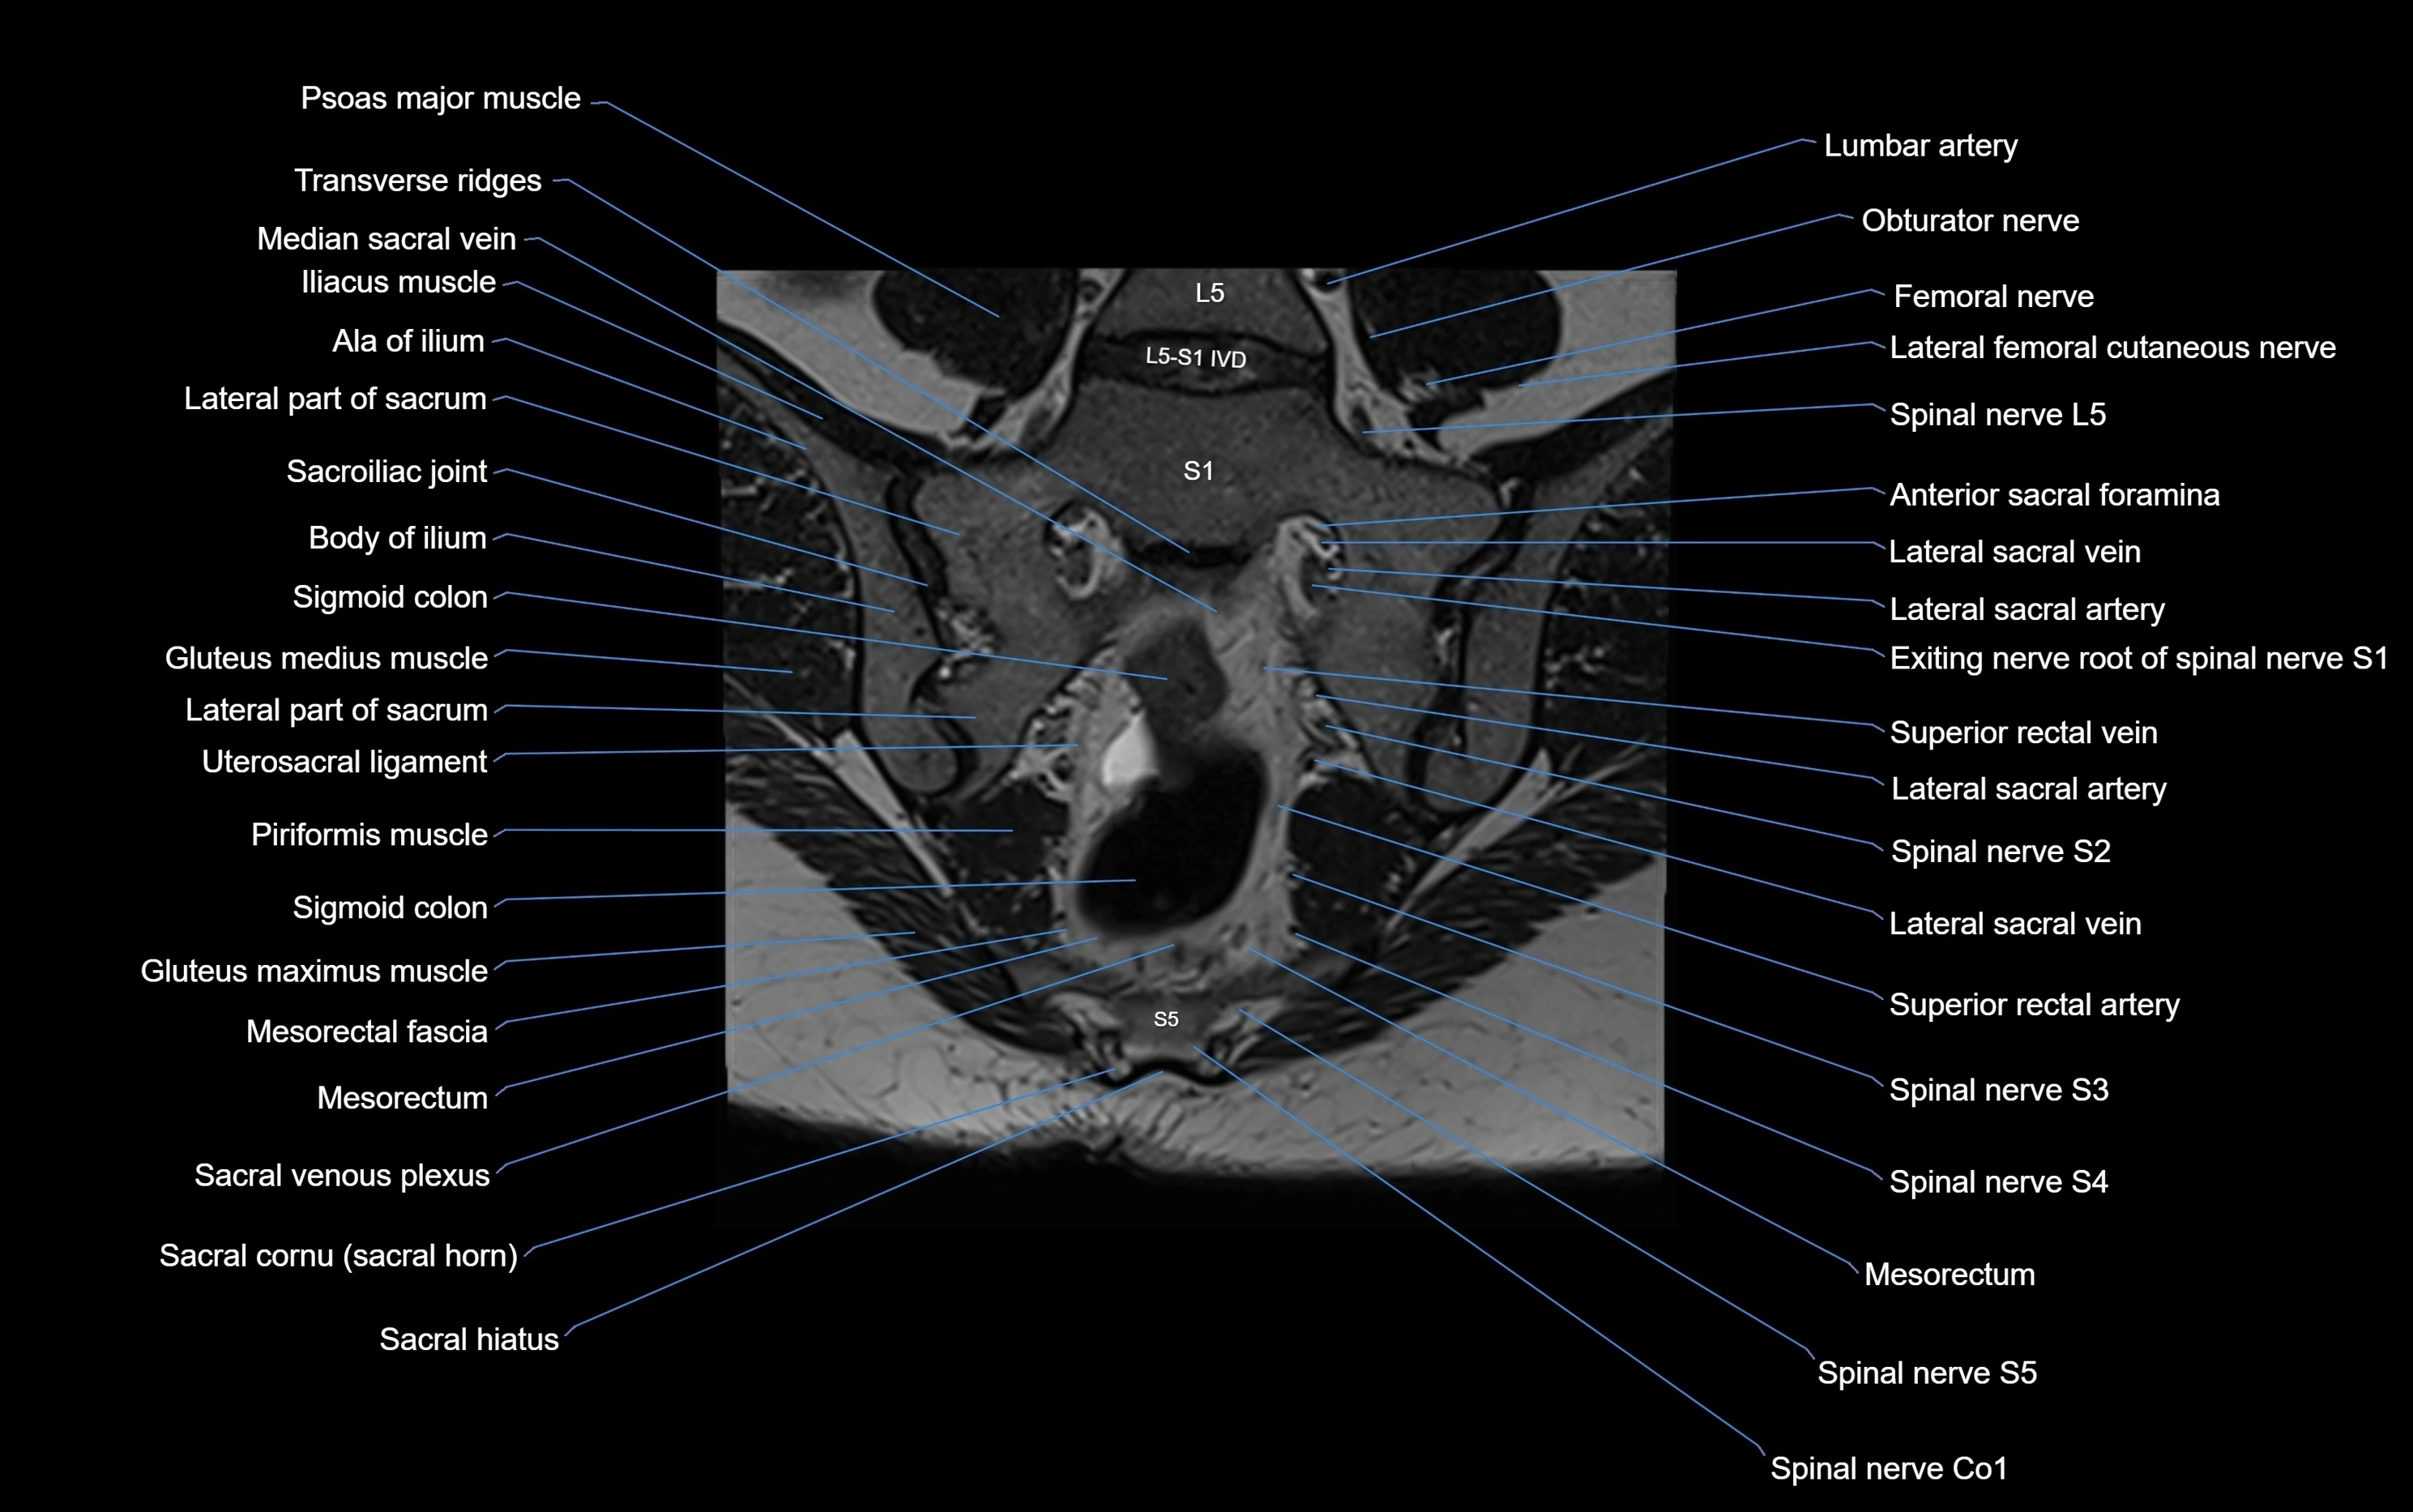

CT image

image